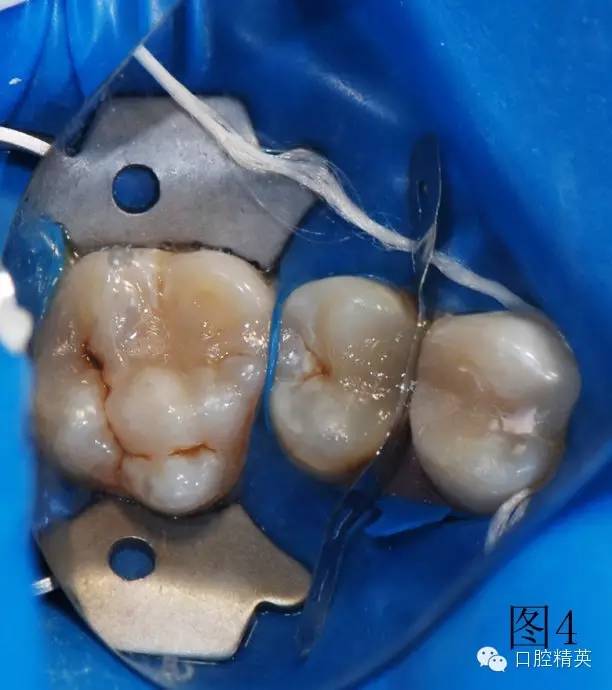

圖2、3為左上第一前磨牙充填結(jié)束,上橡皮障,充填另外兩顆牙。使用橡皮障,可以嚴(yán)密隔濕,防止樹脂受到污染,增加樹脂與牙齒之間的粘結(jié)力,延長充填物的使用壽命。

3顆牙充填完畢,卸下橡皮障夾和障布。